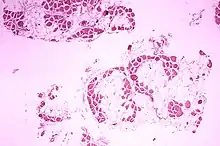

Microscopic image of cross-sectional calf muscle from a person with Duchenne muscular dystrophy, showing extensive replacement of muscle fibers by fat cells.

DMD causes progressive muscle weakness due to muscle fiber disarray, death, and replacement with connective tissue or fat.[3] The voluntary muscles are affected first, especially those of the hips, pelvic area, thighs, calves.[10][11] It eventually progresses to the shoulders and neck, followed by arms, respiratory muscles, and other areas.[11] Fatigue is common.[12]